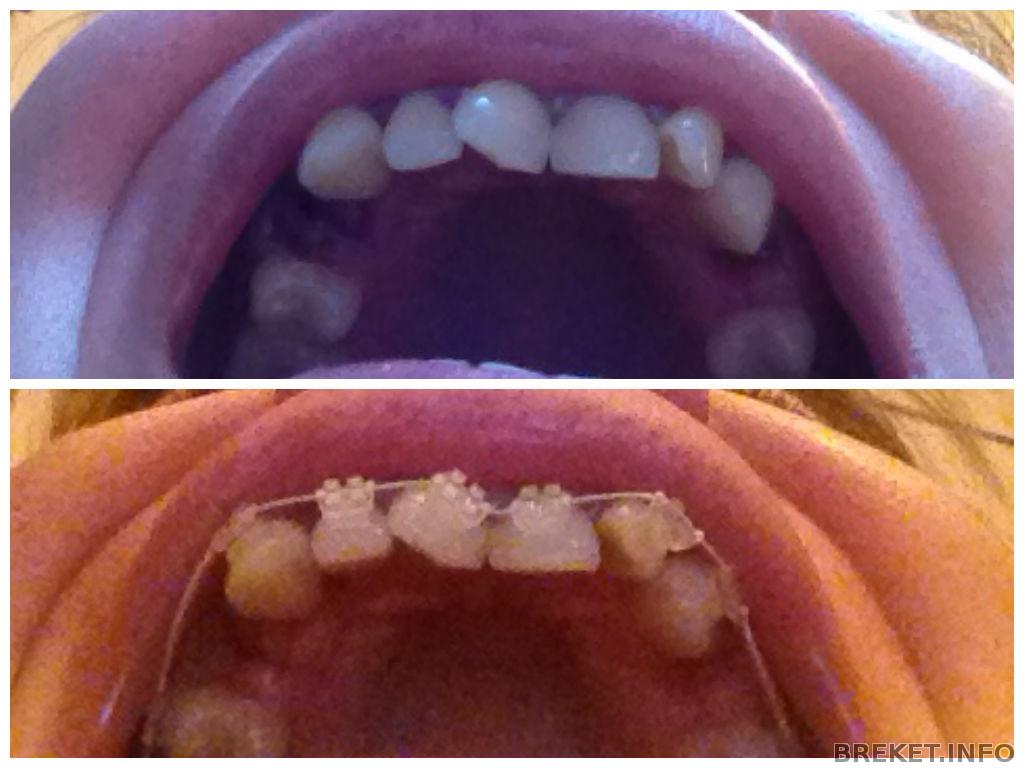

И, ура, вчера ВЧ была закована!

При накусывании болит, клык уже даже как-то немного поменял положение (говорит язык), ну и конечно ночь прошла практически без сна.

Reflection, что за БС не знаю... керамические с лигатурами. Про даймоны ортодонт говорила, что они ей не нра. Собирались ставить самолигирующиеся, какой-то другой фирмы, но в них металлические замочки, а у меня аллергия на металл в анамнезе, пришлось перестраховаться и согласиться на лигатурки.